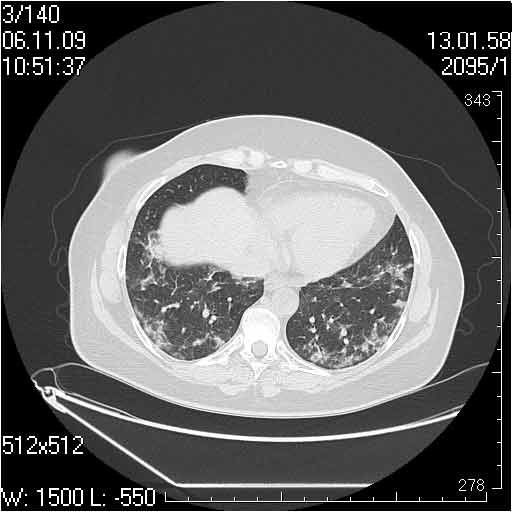

Случай №2

Мужчина 54 лет

Случай 2: картина патологических изменения довольно типична: GGOs & thickened interlobular septas = "crazy paving" sign. Наличие плотностей по типу матового стекла в сочетании с утолщением междолевых перегородок, даёт признак булыжной мостовой; на первом месте будет стоят диагноз альвеолярных протеиноз.